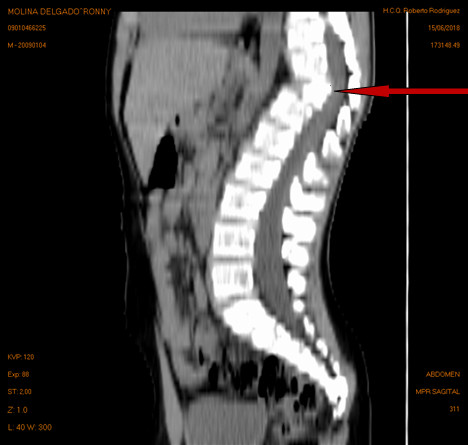

Volver a los detalles del artículo Tuberculosis vertebral